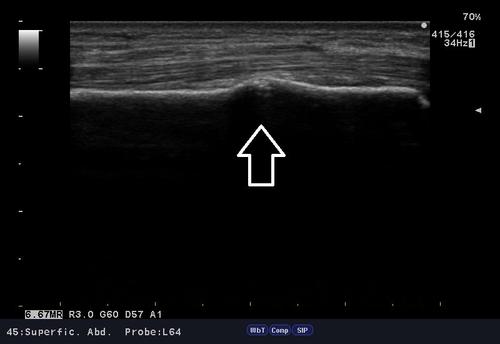

自転車で転倒した際、左手を突いた時に、手首を痛めたと御来院。

問診、視診、触診、そしてエコー検査。

結果「橈骨遠位端部骨折」の部位を確認。

腫れ具合から骨折の有無はある程度予想できますが、エコー検査は骨折の箇所を的確にその場で確認でき、骨癒合を促進させるマイオパルス(MYO PULSE)という治療器で、治療を行えるので強い味方です。